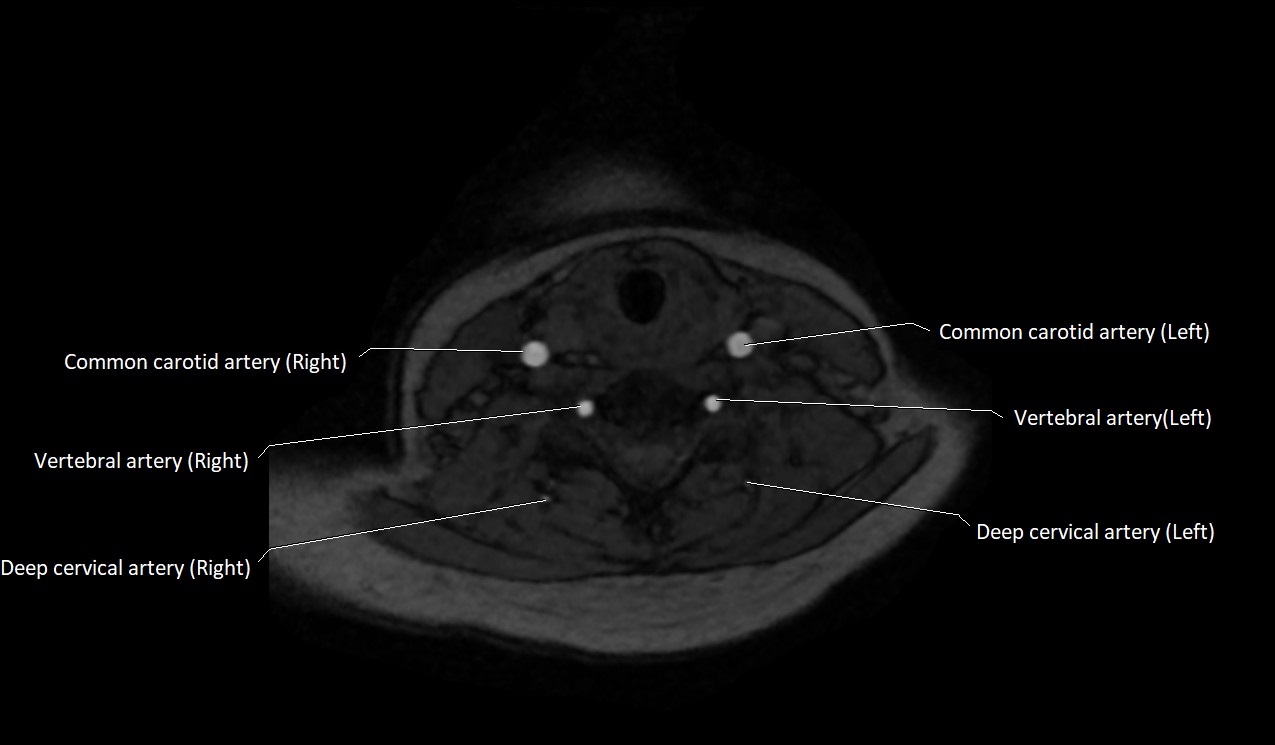

MRI images

image